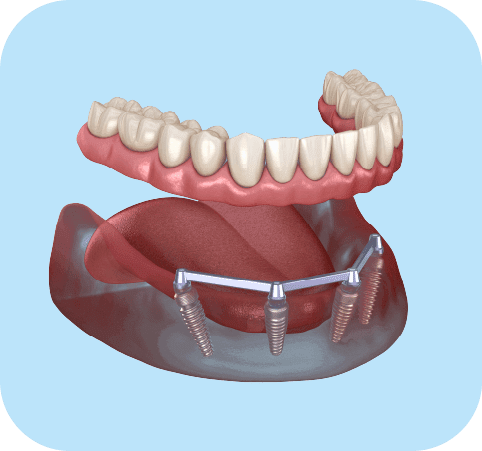

Rehabilitation All-on-4 Implants Treatment

From

4 titanium dental implants (per arch)

4 prosthetic pillars

Hybrid fixed prosthesis

Metal reinforcement bar

Comprehensive treatment for edentulous patients or those with advanced tooth loss. Provides stability, aesthetics, and functionality in a single arch.